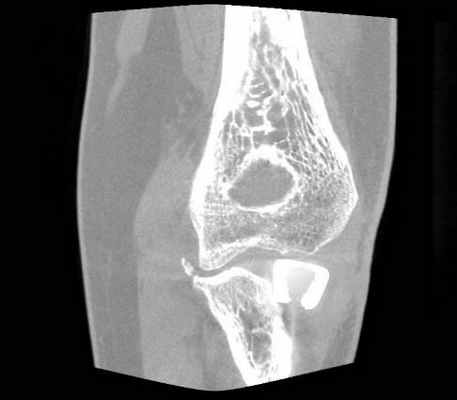

Выполнена гипсовая иммобилизация в функциональном положении. Для уточнения диагноза и предоперационного планирования пациентке выполнено КТ-исследование (рис. 2).

Данный перелом можно классифицировать по классификации Mason как тип 3, по классификации АО - 21C3. Учитывая молодой, трудоспособный возраст пациентки, высокие функциональные требования, и сложность перелома - методом лечения выбрано эндопротезирование головки лучевой кости.

Во время операции выявлен многооскольчатый перелом головки лучевой кости (рис. 3, рис. 4).